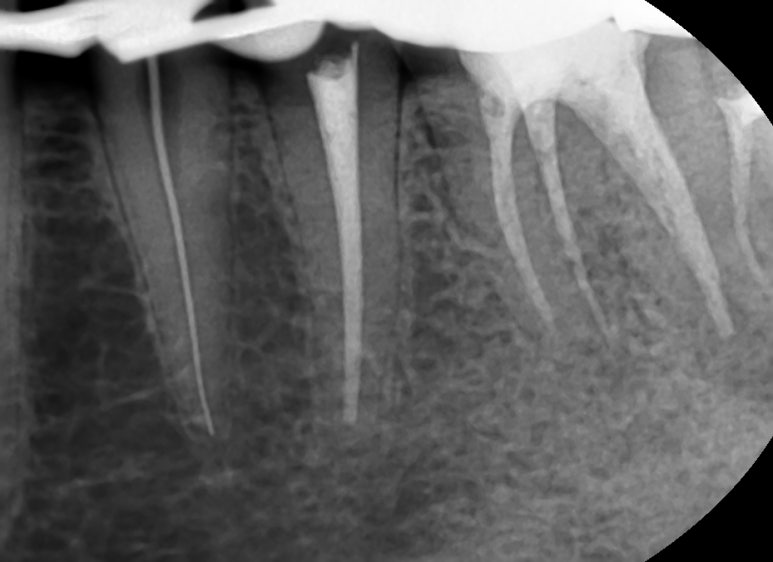

이런 치료과정을 거쳐 신경치료를 하였습니다.

결국 2019년에는 인레이 정도로 끝날 수 있었던 치료가

2021년에는 충치가 더 진행되고 치아가 깨져 신경치료와 크라운치료가 필요한 상태가 되어 신경치료와 크라운을 하게 되었죠.